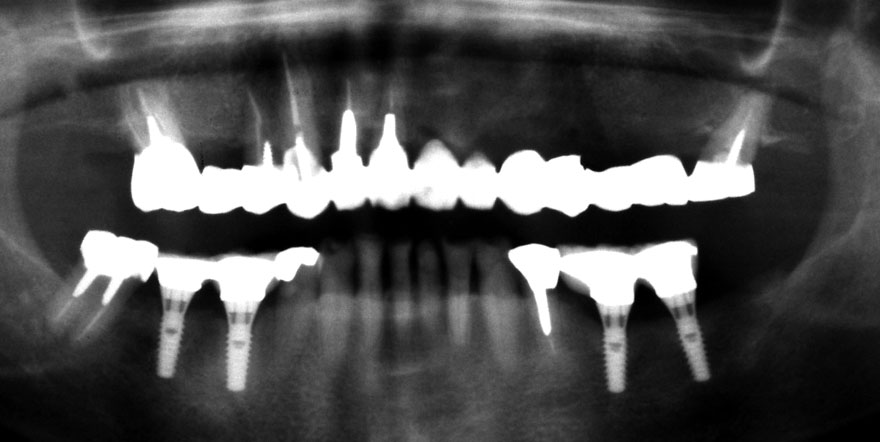

開始年齢 40代

初診時 40歳 女性 平均歯槽骨喪失量:3.14mm

32年後 72歳

平均歯槽骨喪失量:3.22mm

32年間喪失量:-0.08mm

年間喪失速度:-0.002mm

(ケア頻度:1.86ヵ月ごと)